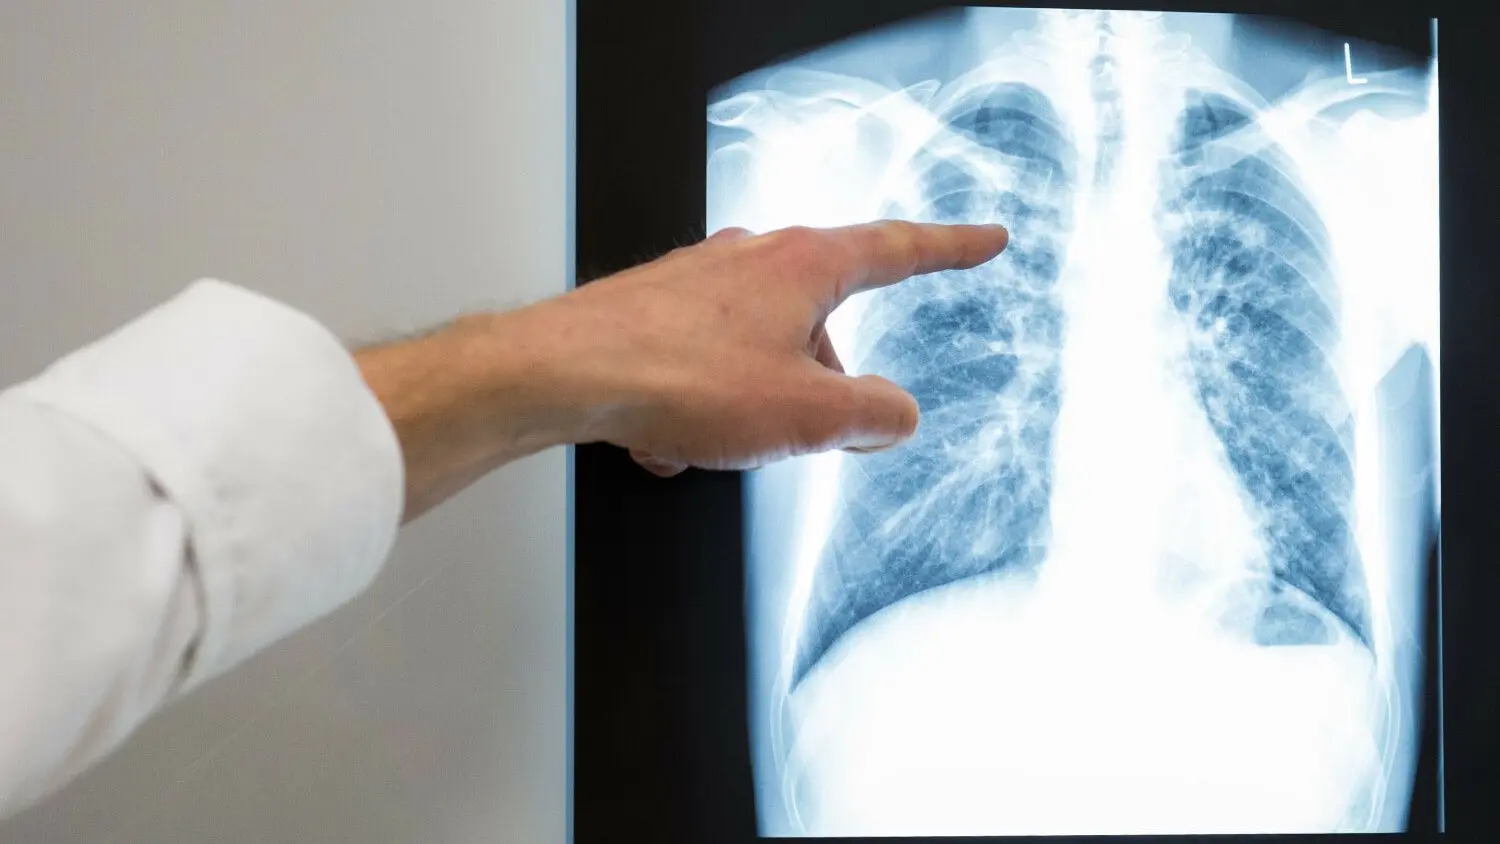

Tuberkulose in Chemnitz: Ein Arzt zeigt auf das Röntgenbild einer Lunge. Nicht jede Infektion muss zwingend zum Ausbruch der Lungenkrankheit führen. Doch in Chemnitz war das nun wiedergholt der Fall.